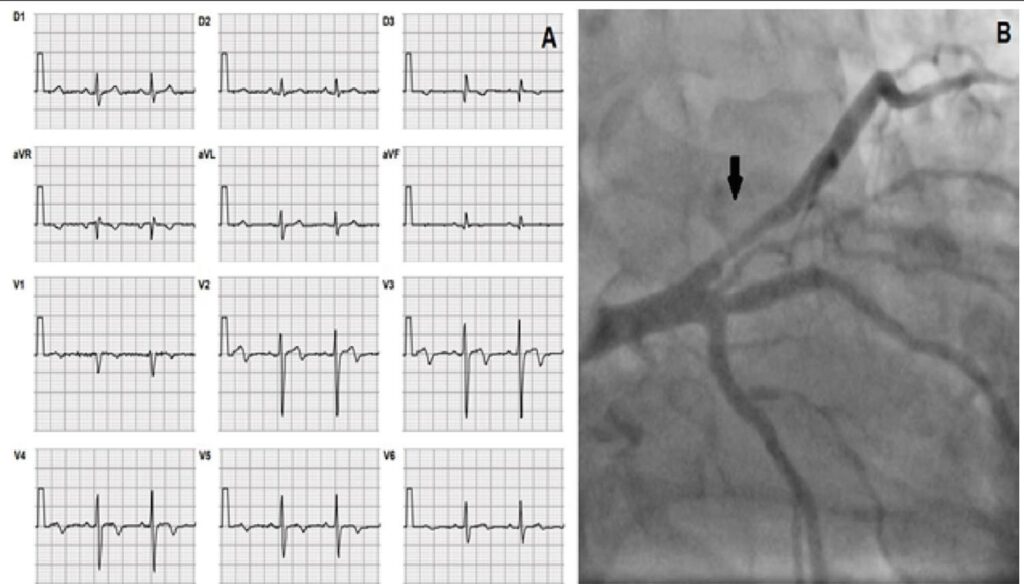

A síndrome coronariana aguda é um dos grandes desafios diagnósticos para o médico na sala de emergência. A complementação com exames de imagem não invasivos, como o ecocardiograma, é ferramenta útil no diagnóstico etiológico de dor torácica. Na suspeita de isquemia, quando o Eletrocardiograma (ECG) e os Marcadores de Necrose Miocárdica (MNM) são inconclusivos, o ecocardiograma pode ser realizado no momento da dor ou imediatamente após. O uso de técnicas avançadas, como a análise da deformação miocárdica (strain), possibilita maior acurácia na identificação do território das coronariopatias.

Relatamos o caso de um paciente com dor torácica na sala de emergência, sem alterações segmentares ao ecocardiograma inicial. Quando usadas ferramentas adicionais (handgrip, strain e pico pós- sistólico), foram evidenciadas alterações de Doença Arterial Coronariana (DAC) significativa, como demonstrado na coronariografia posteriormente.